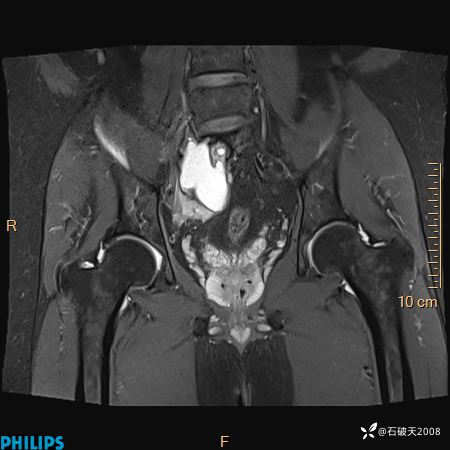

2023年3月份MRI影像

T2压脂冠状位